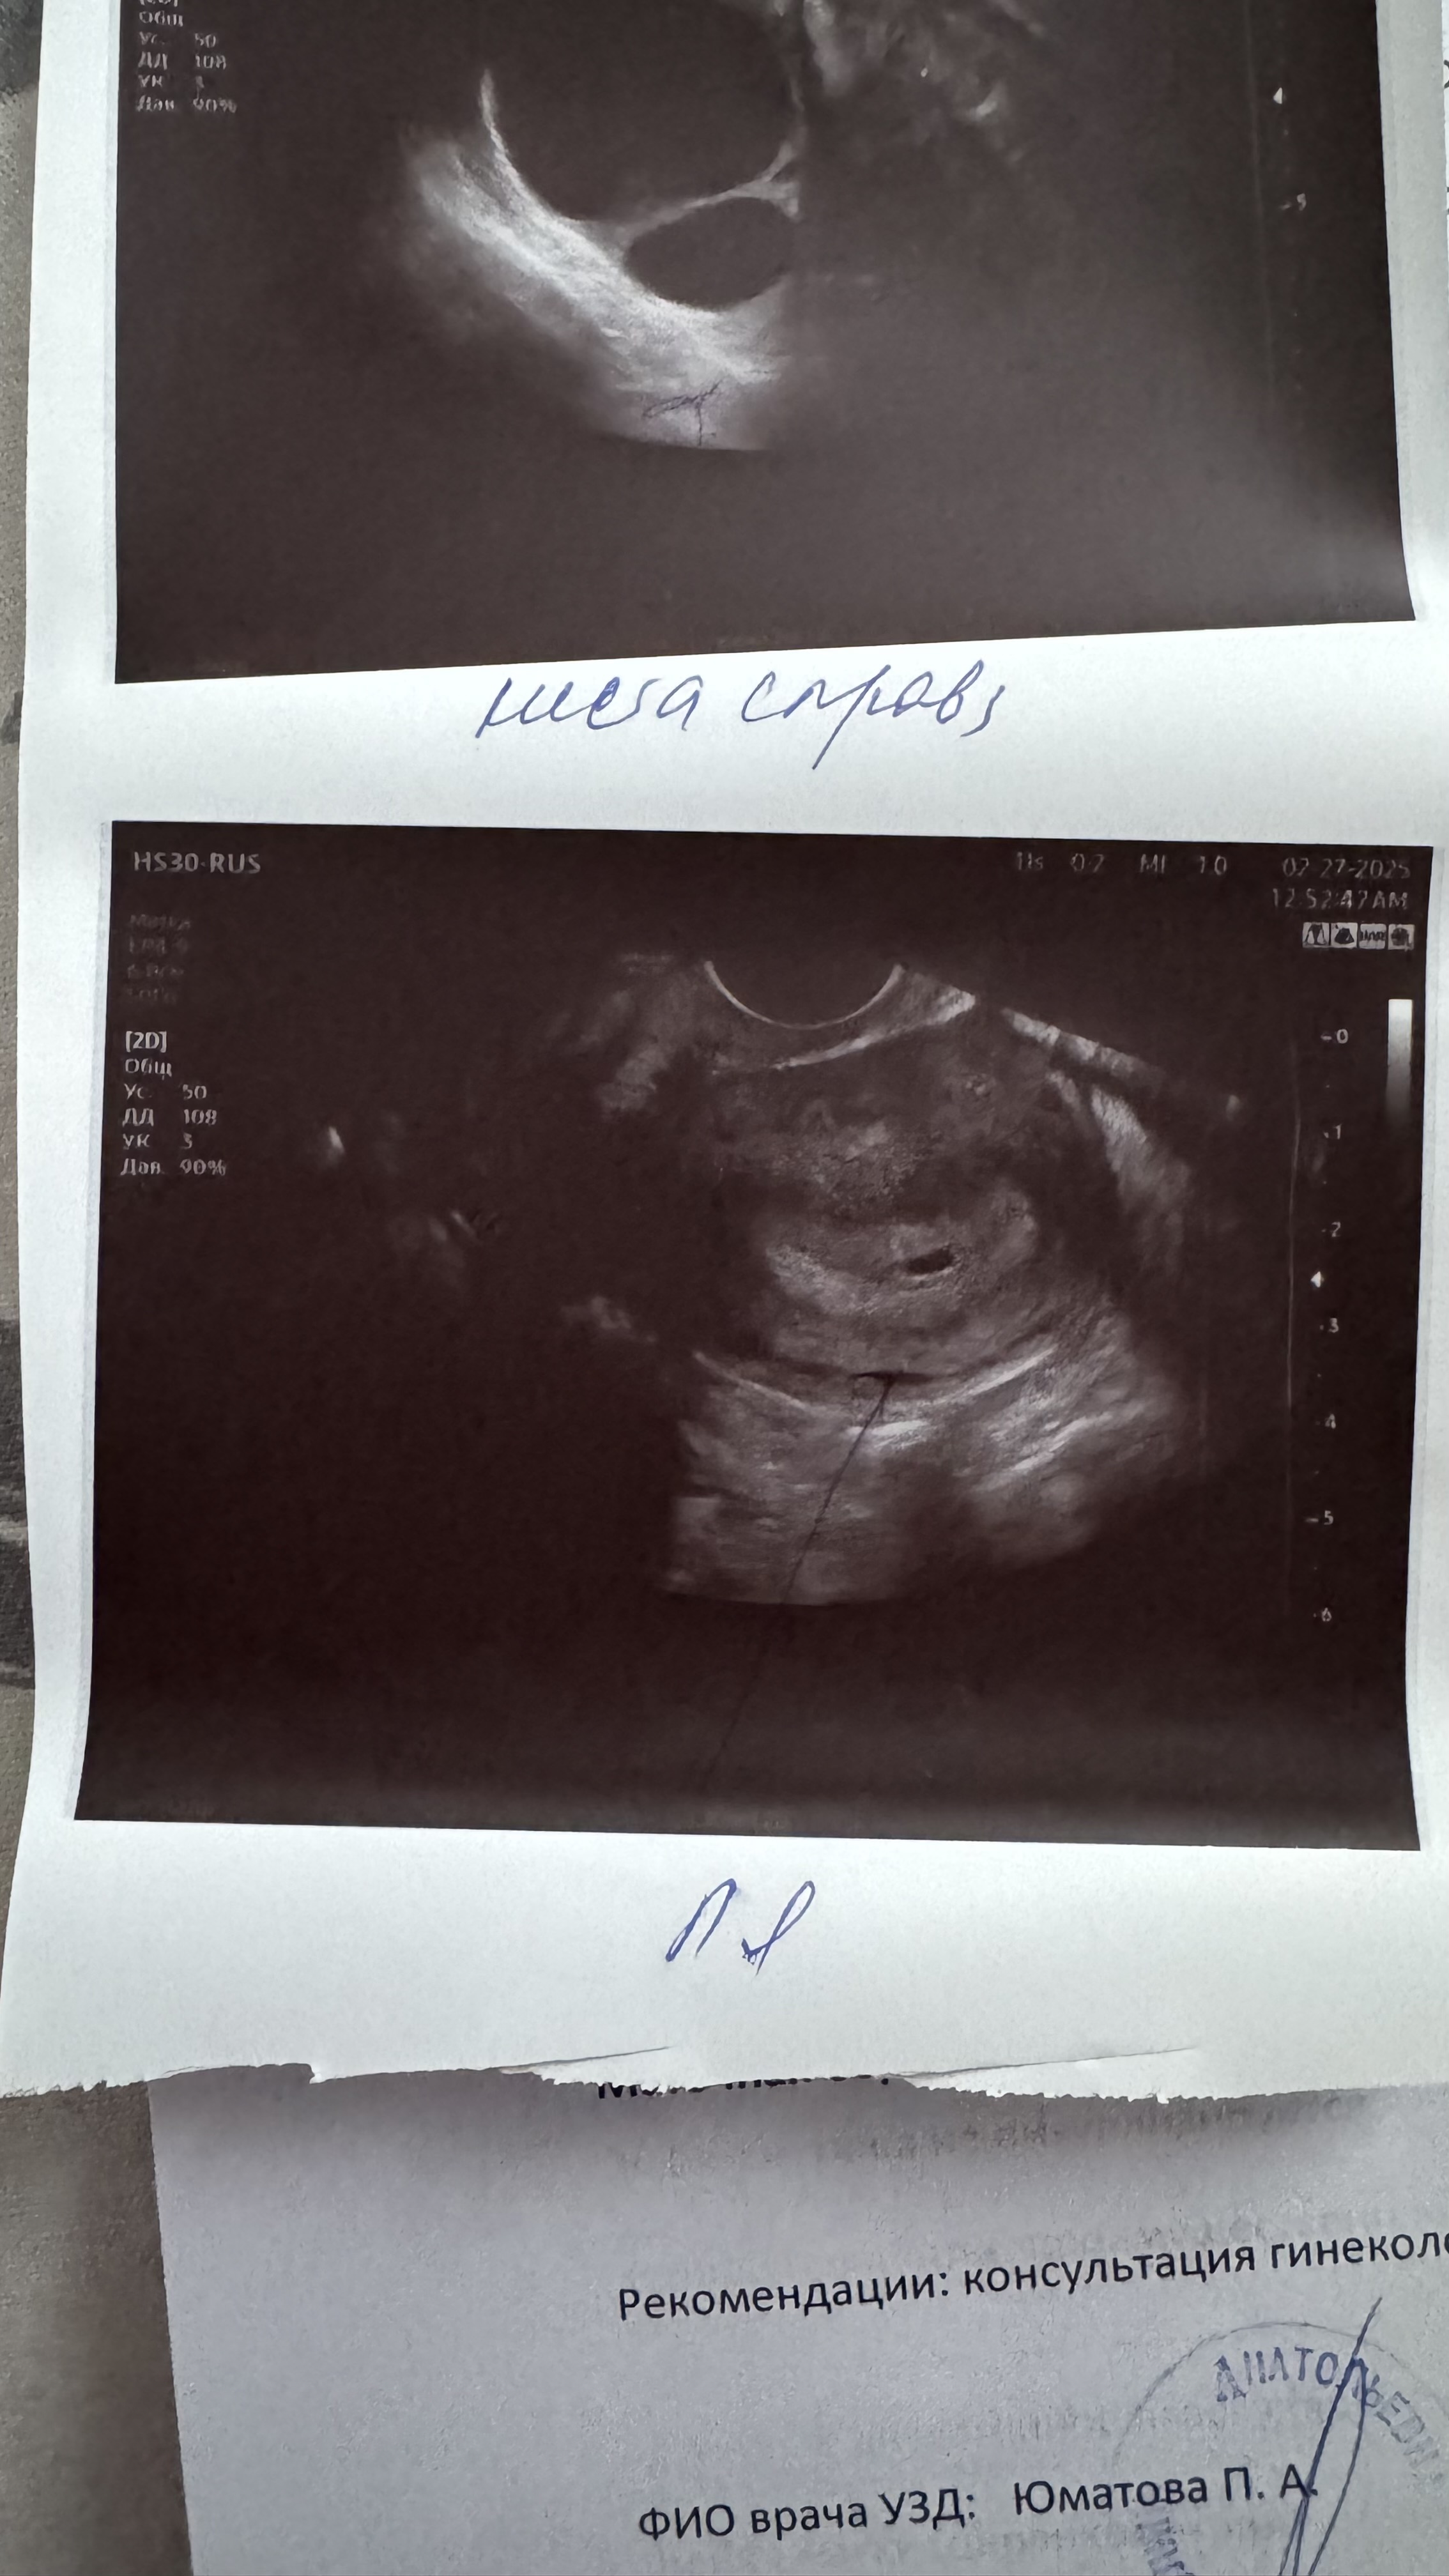

Подскажите на узи написано плацента кольцевидный венчик, это нормально ?

В заключение пишут ли о пя деформировано ли о нормальной/овальной формы Кольцевидный хорион, да, норма до 16н

Здравствуйте! Подскажите, чем ваш истрия закончилась? А то по узи видят такую же картину - вытянутое плодное яйцо.